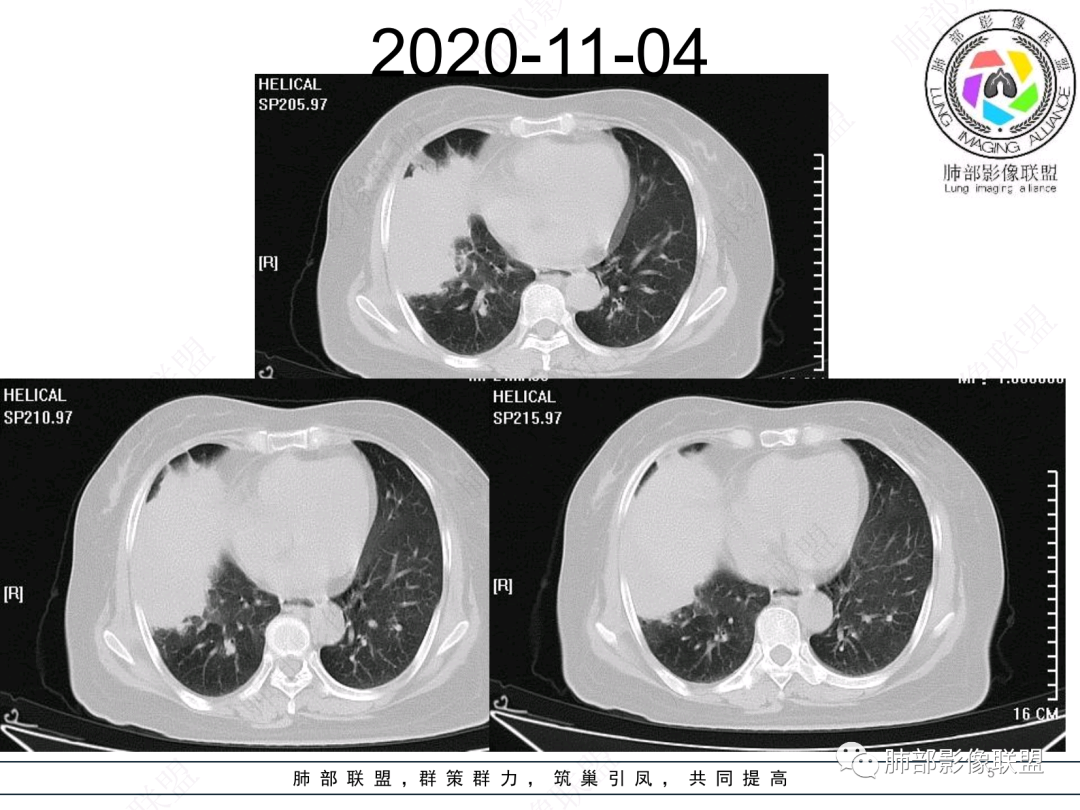

慢性咳嗽,抗炎复查无好转,原右肺中叶实边,外侧段支气管开口阻断,复查无好转,逐渐向下叶外前基底段融合形成大肿块,边缘膨隆,密度不均匀,坏死轮廓不清,内血管束破坏,累及中轴间质厚,外围分布,方向恶性,与炎性肉芽肿鉴别,隐球荚膜抗原先排查!

女,74岁,咳嗽咳痰加重一周入院,右肺中叶大片实变影,边界清晰,病灶内密度不均匀,右肺中叶支气管变窄,增强扫描病灶明显强化,考虑恶性病变能,鉴别肺脓肿。

右肺中叶实变,支气管开口阻断,边缘膨隆,密度不均匀,坏死边界清晰,胸膜累及,。一般抗感染治疗无效。考虑恶性。

老年女性患者,慢性病程,两次活检均提示炎性病变,胸部CT:右肺中叶大片实变密度影,边界尚清楚,部分收缩,部分膨隆,内部有低密度坏死,坏死边界清楚,无明显结节感,无分割,总体考虑炎性病变,机化性肺炎,NTM,慢性肺脓肿,鉴别:恶性,腺癌

右肺中叶大片实变,内见大片的坏死,中叶外侧段支气管阻塞,相邻胸膜增厚,间隔约四个月后复查,发现低密度坏死内可见气泡影,老年人,反复迁延不愈的病变要考虑恶性,首先考虑腺癌伴感染。鉴别慢性脓肿。

右肺胸膜下实变,跨叶,形态不规则,局部边缘膨隆,中叶支气管外侧段进入后阻塞伴不张,不均匀强化,其内坏死边界欠清晰,复查无吸收,考虑腺癌,鉴别慢性炎症伴脓肿

右肺大片状高密度灶,跨叶,密度不均,边缘膨隆,支气管阻塞,粘液栓,不均匀强化,其内坏死边界欠清晰,复查无吸收,考虑腺癌,鉴别慢性炎症,脓肿

胸部CT:右肺中下叶大片实变影,界清,边缘膨隆为主,中叶外侧段支气管截断。增强不均匀强化,边缘可见血管影迂曲模糊,内见条带状低密度影。治疗后病变进展。考虑恶性,鳞Ca?鉴别TB、OP。

老年女性,慢性病史,炎性指标稍高,肿标正常,右中下肺大片实变,跨叶生长,边界清,收缩力差,膨隆生长为主,支气管杵状截断,均匀强化,其内坏死边界清,可见悬浮气泡,整体观察,病灶膨隆生长为主,邻近肺野无播散灶,形态单一,尽管慢性病史,影像不支持OP和TB,支气管截断呈杵状,肿标正常,均匀强化,虽是高龄患者,诊断恶性肿瘤有点牵强,综和分析,首选炎性病变放线菌感染,其次考虑低度恶性占位炎机母。